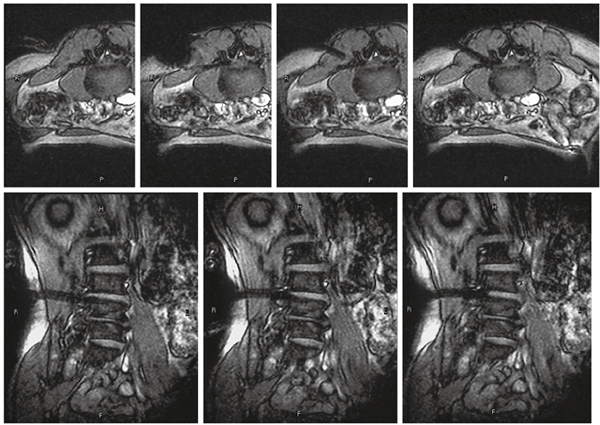

機能領域のうち,特に重要な運動にかかわる神経線維である錐体路を描出するため,DWI やDTI (拡散テンソル画像)を用いた方法が試みられてきたが,術中では手術操作に伴い脳実質が変形(ブレインシフト)するため,術中撮像により画像を更新することが望ましい。術中DWIを用いた手術ナビゲーションにより,術中の錐体路を含む白質神経束の位置の確認,術中の錐体路のシフトの定量的評価,描出された錐体路の電気刺激による妥当性検証が可能となり,患者の運動機能の保護に役立っている。